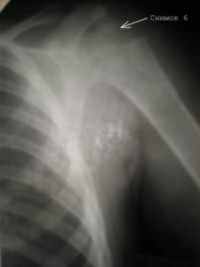

Снимок 6 (21.08.04) – полное анатомическое и структурное восстановление проксимального отдела правой плечевой кости в сравнении с левым плечевым суставом (Снимок 7).